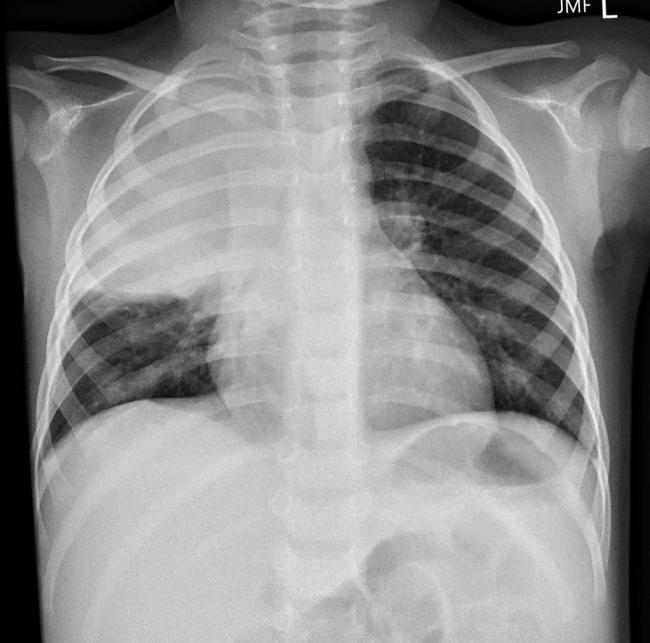

Локализация процесса вдоль корня легкого затрудняет рентгенологическую диагностику заболевания. Рентген в прямой проекции показывает расширение корня легкого, увеличение тени средостения, но дать более точные характеристики не представляется возможным. Более детальную информацию может дать компьютерная томография. Однако даже при качественном изображении остаются иногда вопросы.

Основным методом диагностики прикорневой пневмонии являются рентгенологические методы исследования. На рентгенограммах врач может увидеть локализацию воспаления, дифференцировать прикорневое воспаление лёгких от других заболеваний дыхательных путей. Но при прикорневой пневмонии интерпретация рентгенографического исследования может быть затруднительной. Затемнение от воспалённого очага часто наслаивается на корень лёгкого. В результате легочный корень на рентгеновском снимке «расширяется», что может указывать на новообразование или туберкулёз.